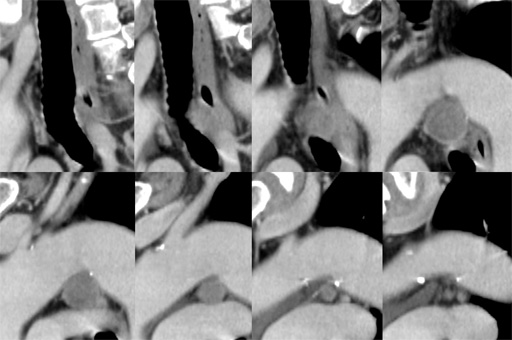

症例7 : 図5 胸部CT 縦隔条件(sagittal image)